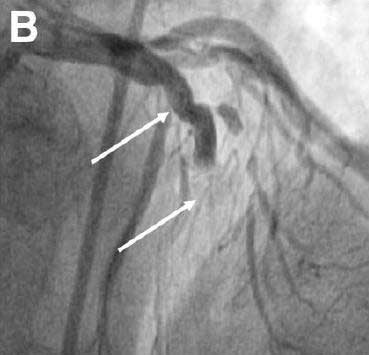

冠状动脉造影

LAD完全闭塞,高度提示一处为血栓的影像位于支架中部(图2箭头处)。

图2